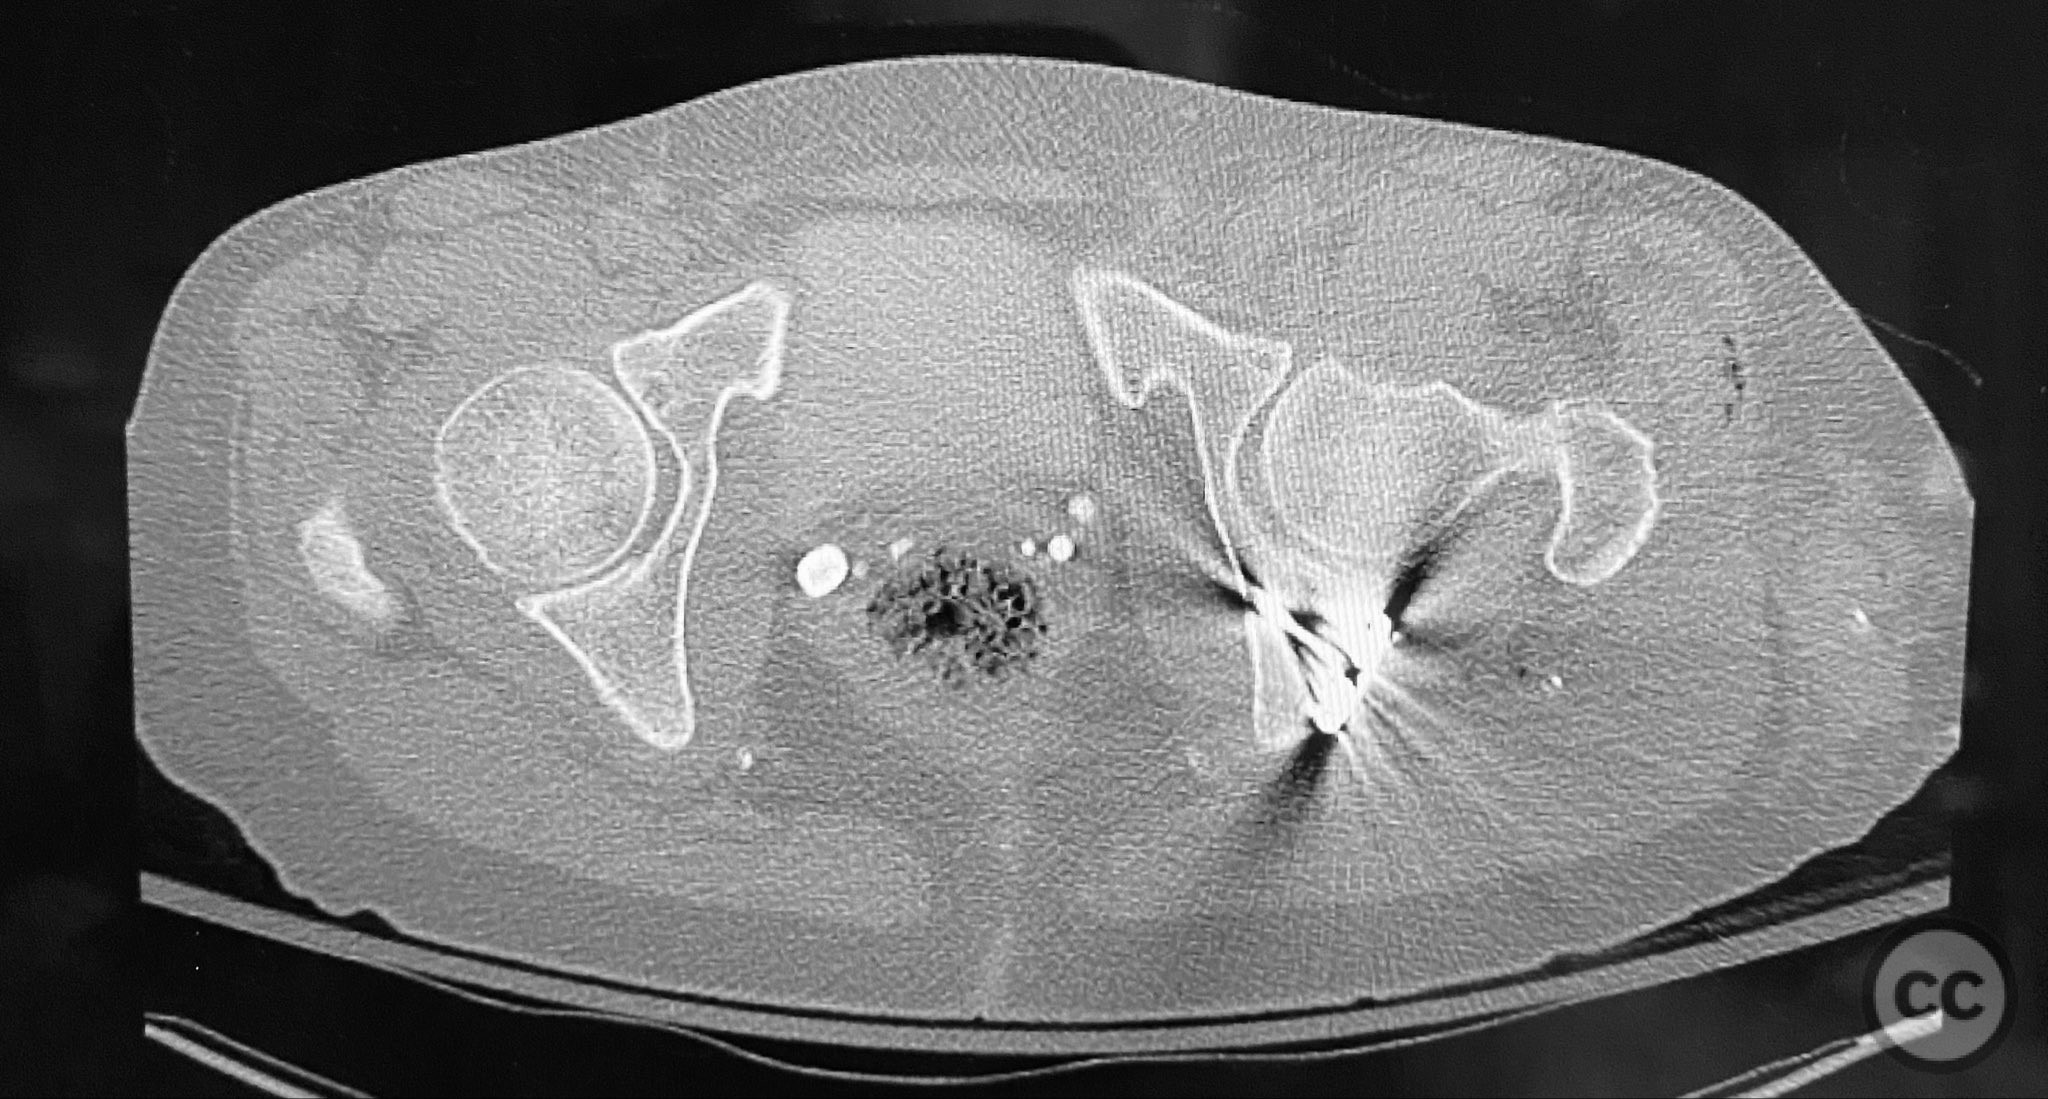

Clinical and radiological findings:  A patient sustained a posterior wall acetabular fracture-dislocation, characterized by comminution of the posterior wall, impaction of fragments into the posterior column region, and intra-articular loose fragments within the fossa acetabuli. Sagittal imaging demonstrated femoral head impalement on the intact wall, raising concern for potential irreducibility. Coronal and axial CT images revealed acetabular and femoral head impactions, peripheral wall comminution, incomplete fracture extension at the acetabular notch and quadrilateral surface, and an articular fragment within the joint. Surface renderings confirmed the extent of peripheral wall comminution and impaction. Despite these findings, a closed manipulative reduction was successfully achieved, resulting in a congruent reduction on post-reduction imaging.